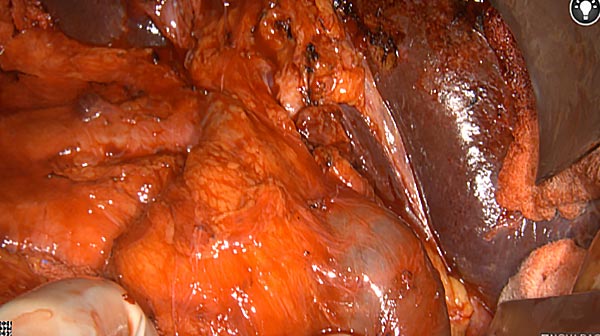

Intraoperative imaging panitumumab-IRDye800 (fluorescence)

Primary tumor prior to resection

Wound bed post re-resection of tumor

Fluorescence imaging of the tumor was performed prior to resection and after resection to “check” the wound bed. In the upper row the tumor is clearly visible with fluorescence and in the bottom row you can see that the wound bed is empty – there is no suspicious fluorescence left. The middle column of tiles show the fluorescence signal in black and white where the “white” represents the tumor and the black the background (= no fluorescence signal). The right column of tiles shows the overlay of the brightfield photo (in greyscale) and the fluorescence (red-yellow-blue heatmap). This image provides anatomical context to the surgeon – the surgeon can see where is the fluorescence located with regard to the tumor area.